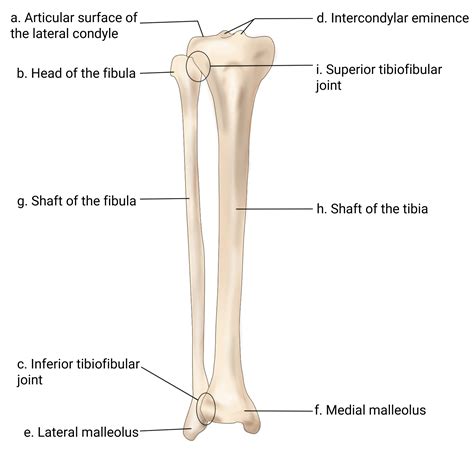

The superior tibiofibular joint (STJ) is often an overlooked part of the low-toned limb energising chain. While much attention in clinical settings is point toward the genu or the ankle, this small, synovial joint play a crucial role in the biomechanics of movement. Located just below the knee, it serves as the joint point between the lateral condyle of the shinbone and the head of the fibula. Although it does not bear significant weight, its functional unity is vital for ankle stability, shock absorption, and the efficient transmittal of forces during activities such as walking, running, and jumping.

Anatomy and Structural Composition

See the anatomy of the superior tibiofibular joint requires a face at how the shinbone and fibula interact. This joint is classified as a plane synovial joint, qualify by a small joint cavity enclosed by a fibrous capsule. Various key structures conserve the stability of this articulation:

• Articulary Gristle: Both the tibial facet and the fibular mind are extend with hyaline gristle, grant for smooth, glide motility.

• Anterior and Posterior Superior Tibiofibular Ligaments: These ligaments act as the primary stabilizers, reenforce the capsule and restricting excessive movement of the fibular caput.

• Interosseous Membrane: While technically separate, this hempen tissue connects the shaft of the tibia and fibula, work in bicycle-built-for-two with the superior joint to care load dispersion.

• Biceps Femoris Tendon: This major hamstring muscle attaches to the fibular caput, exerting a active influence on the joint's place during knee flexion.